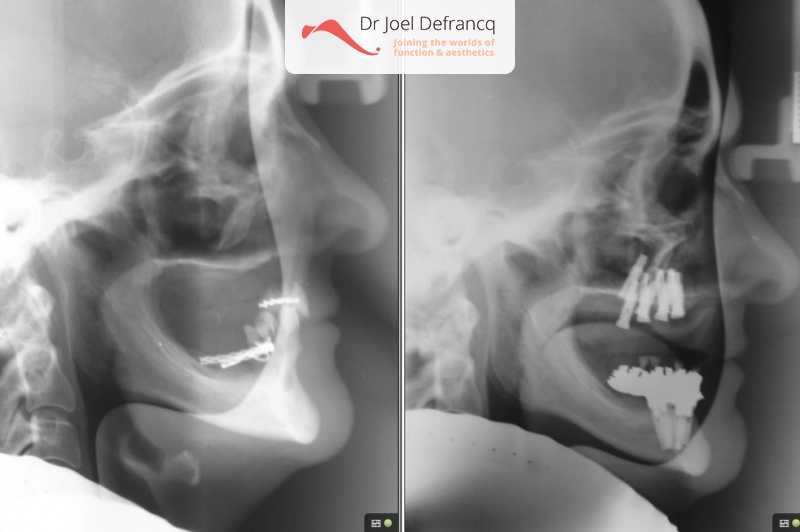

Dentale diagnose

- Open beet

Behandeling tandheelkundige implantaten

- Vaste tanden op implantaten (bovenkaak)

- Vaste tanden op implantaten (onderkaak)